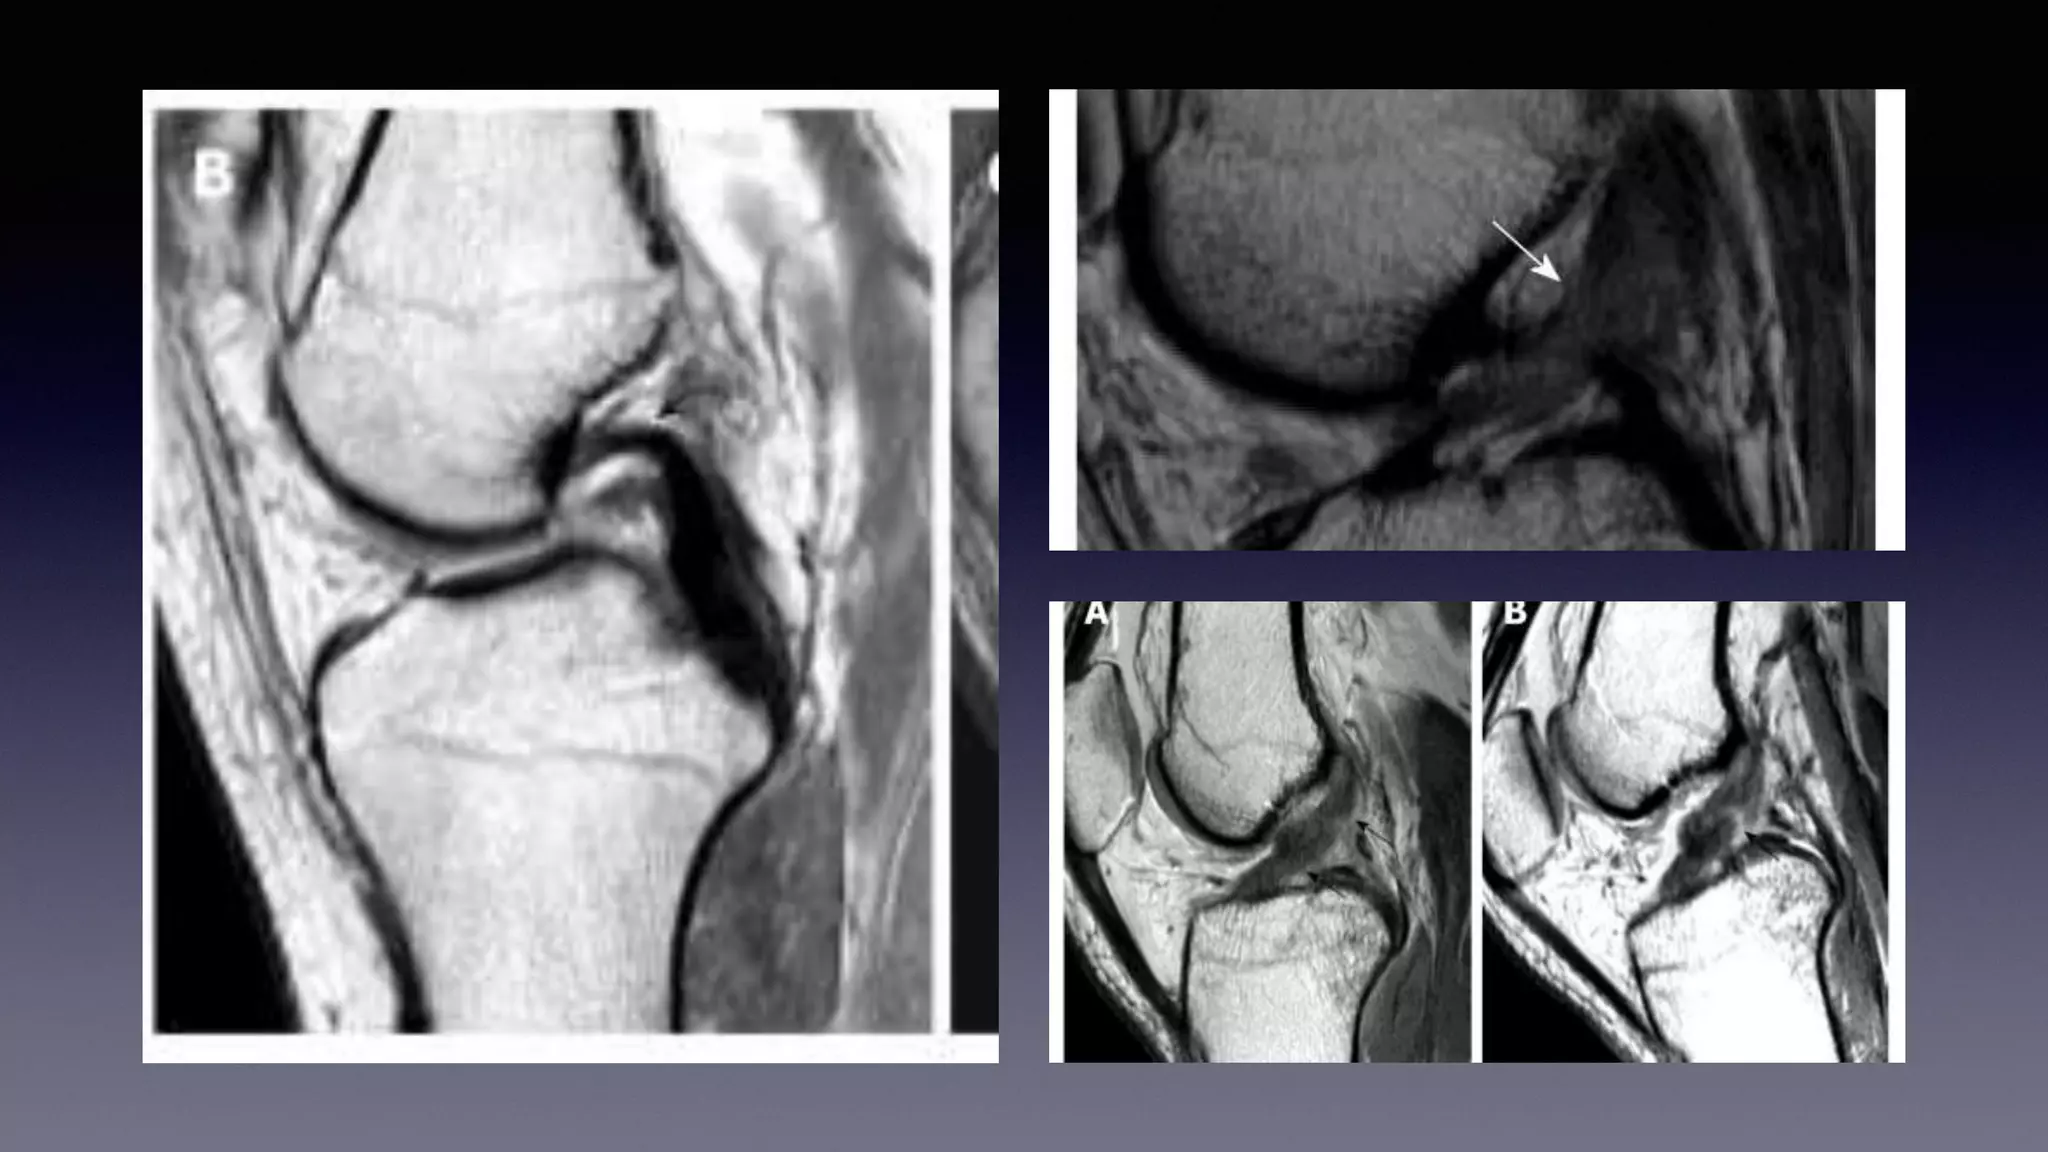

This document discusses using MRI to diagnose ligament injuries in the knee. It begins with an overview of MRI anatomy of the knee and expected pathology. It then discusses specific ligaments like the ACL, PCL, MCL and LCL. For the ACL, it shows images of acute tears, chronic tears and intrasubstance tears. It emphasizes knowing the knee anatomy well and correlating any abnormalities seen with clinical findings in order to apply the appropriate treatment.